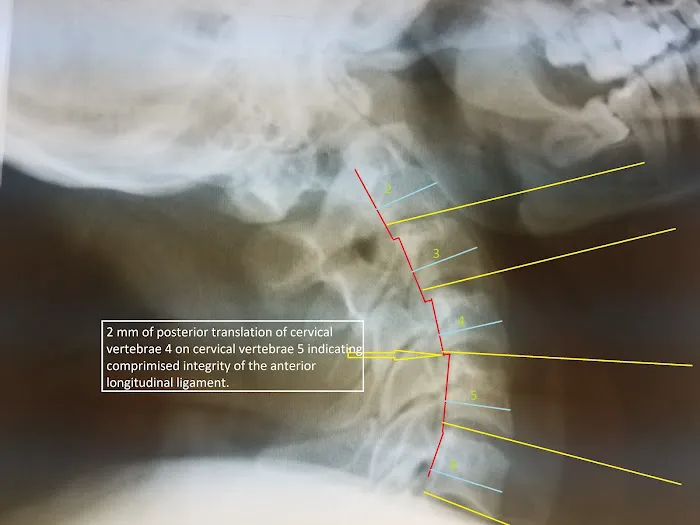

- X-Rays: As part of their diagnostic process, the center has access to X-ray and MRI diagnostics. This allows the doctors to properly document injuries, which is a vital step for creating an effective care plan and for providing accurate information for legal and insurance purposes.